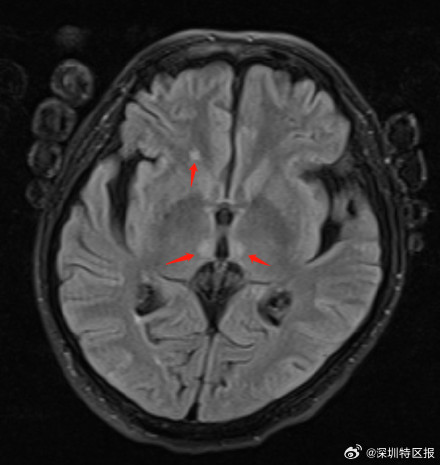

5个多月前,因酗酒厉害突发瘫痪,一名50岁男子被送进急诊,被诊断为“韦尼克脑病及周围神经病”,一度生命垂危。幸运的是,在南山医院多学科团队和外聘专家的协作下,他连闯免疫关、感染关、呼吸关、肌无力关等四大难“关”,在ICU救治130天后成功脱险,创造了生命奇迹。